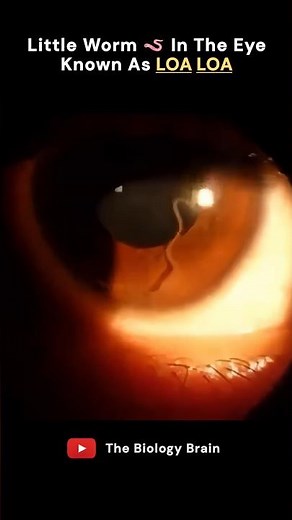

Worm Parasite - Eye Worm

Loa Loa - Real

Parasites - Loa Loa